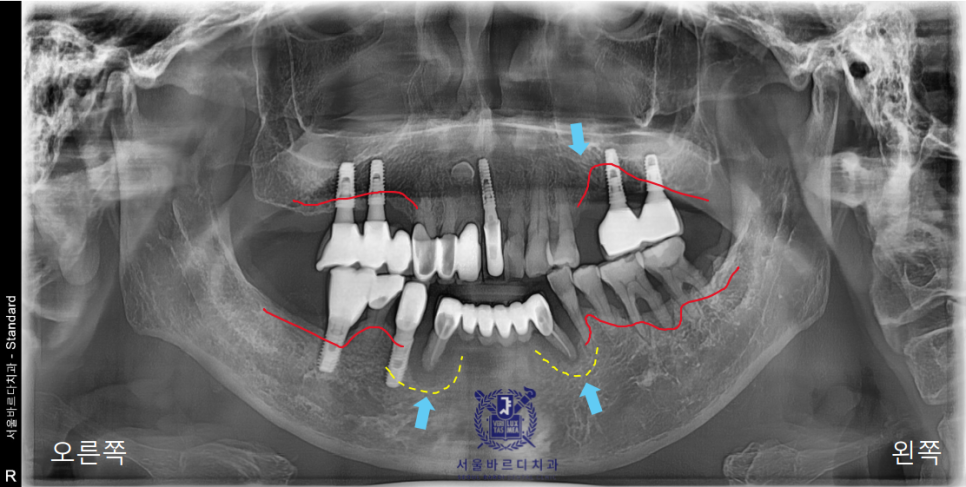

일단 파노라마 사진을 찍어 전체적인 상태를 체크해드렸습니다.

이미 다수의 보철과 임플란트를 하셨고,

앞니쪽은 조금 더 자세하게 보기위해 치근단 엑스레이를 추가로 촬영하였습니다.

양쪽 송곳니 두개를 이용해 앞니 6개의 보철을 사용하고계셨는데

지지해주던 양쪽 송곳니쪽에 문제가 생겨서

염증이 이미 많이 진행된 상태였습니다.

노란색으로 표시된 곡선의 움푹 들어간 부분이

실제로 수술시에 육안으로 잘 보이지 않기 때문에

손으로 만져보면서 조심스럽게 진행해야합니다.

또 너무 뒷쪽으로 식립하게 되는 경우

파란색 선 뒷쪽에 위치한 혀쪽의 설동맥과 가까워지게 되는데

설동맥을 건드린 경우는 대량의 출혈이 일어나게 됩니다.